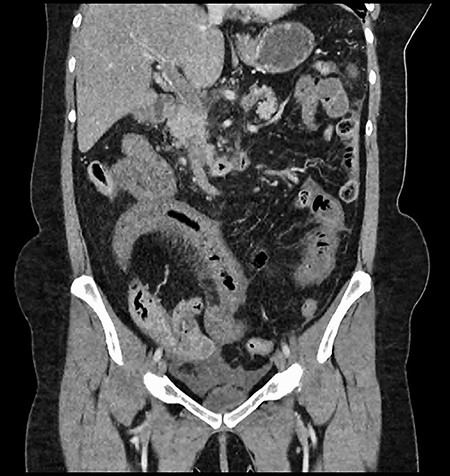

A 61-year-old female presented to a regional hospital with a 3-week history of intermittent diarrhoea, vomiting and generalized abdominal pain. She had a diffusely tender abdomen but was not peritonitic, and was shocked with a heart rate of 110 beats per minute, blood pressure of 89/45 mmHg and was peripherally cool. Her blood tests revealed a lactate of 7.2 mmol/L, which worsened to 7.8 mmol/L during resuscitation with intravenous fluids, and white cell count was 30.9 × 109/L, with an international normalized ratio (INR) of 1.4. She had an acute kidney injury with a creatinine of 119μmol/L and estimated glomerular filtration rate (eGFR) of 43 mL/min/1.73m2. Computed tomography (CT) revealed extensive thickened loops of non-enhancing small bowel with pneumatosis, moderate free fluid and a large splenic infarction. There was extensive thrombosis of the splenic vein and superior mesenteric vein extending into the portal vein to the level of the porta hepatis. Her background history included factor V Leiden and protein S deficiency, for which she had been non-compliant with warfarin during this illness. She had no surgical history (Figs. 1–5).

CT showing an area of splenic infarction due to venous ischaemia.